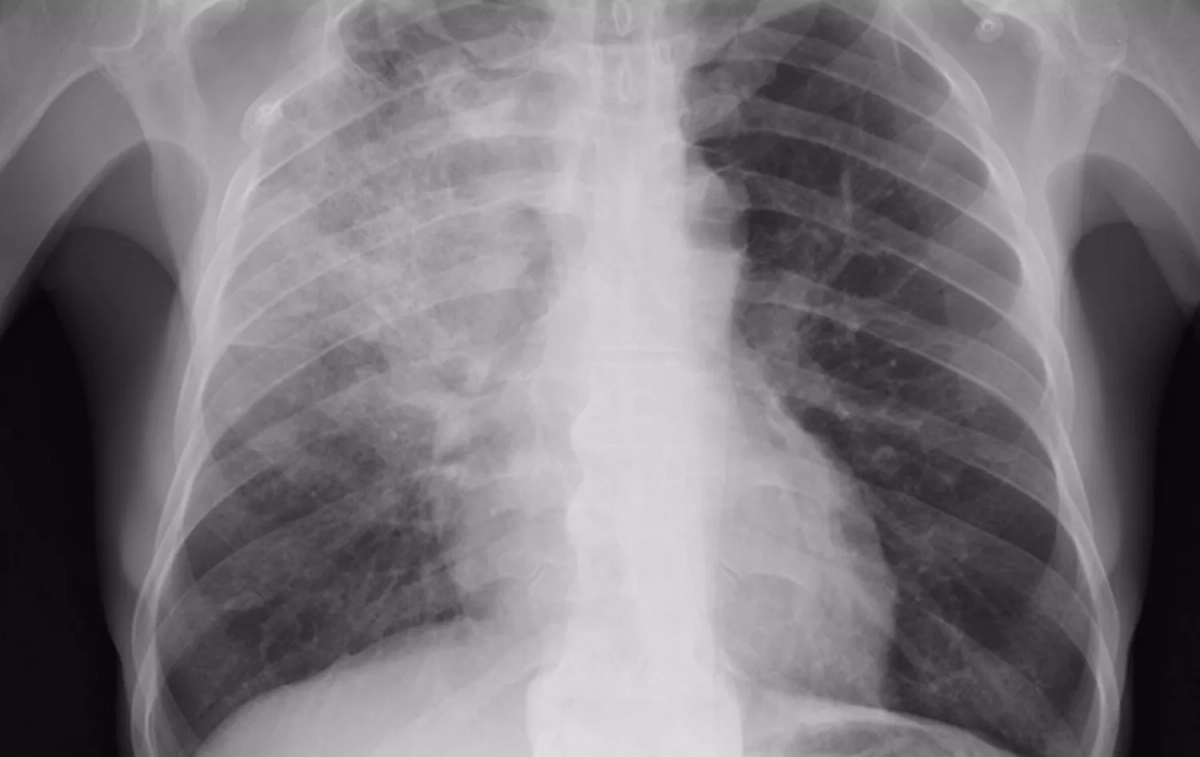

A pneumonia é a infecção do pulmão por bactérias como o neumococo, por vírus como a gripe ou o Covid-19, ou por vírus e bactérias ao mesmo tempo. Estas infecções produzem inflamación e dano no tecido dos pulmões levando os alvéolos pulmonares de pus e líquido e impedindo o correcto intercâmbio de ar para a oxigenación do sangue e a eliminação de dióxido de carbono ao exterior. É muito frequente, sobretudo, na estação que já assoma: o inverno.